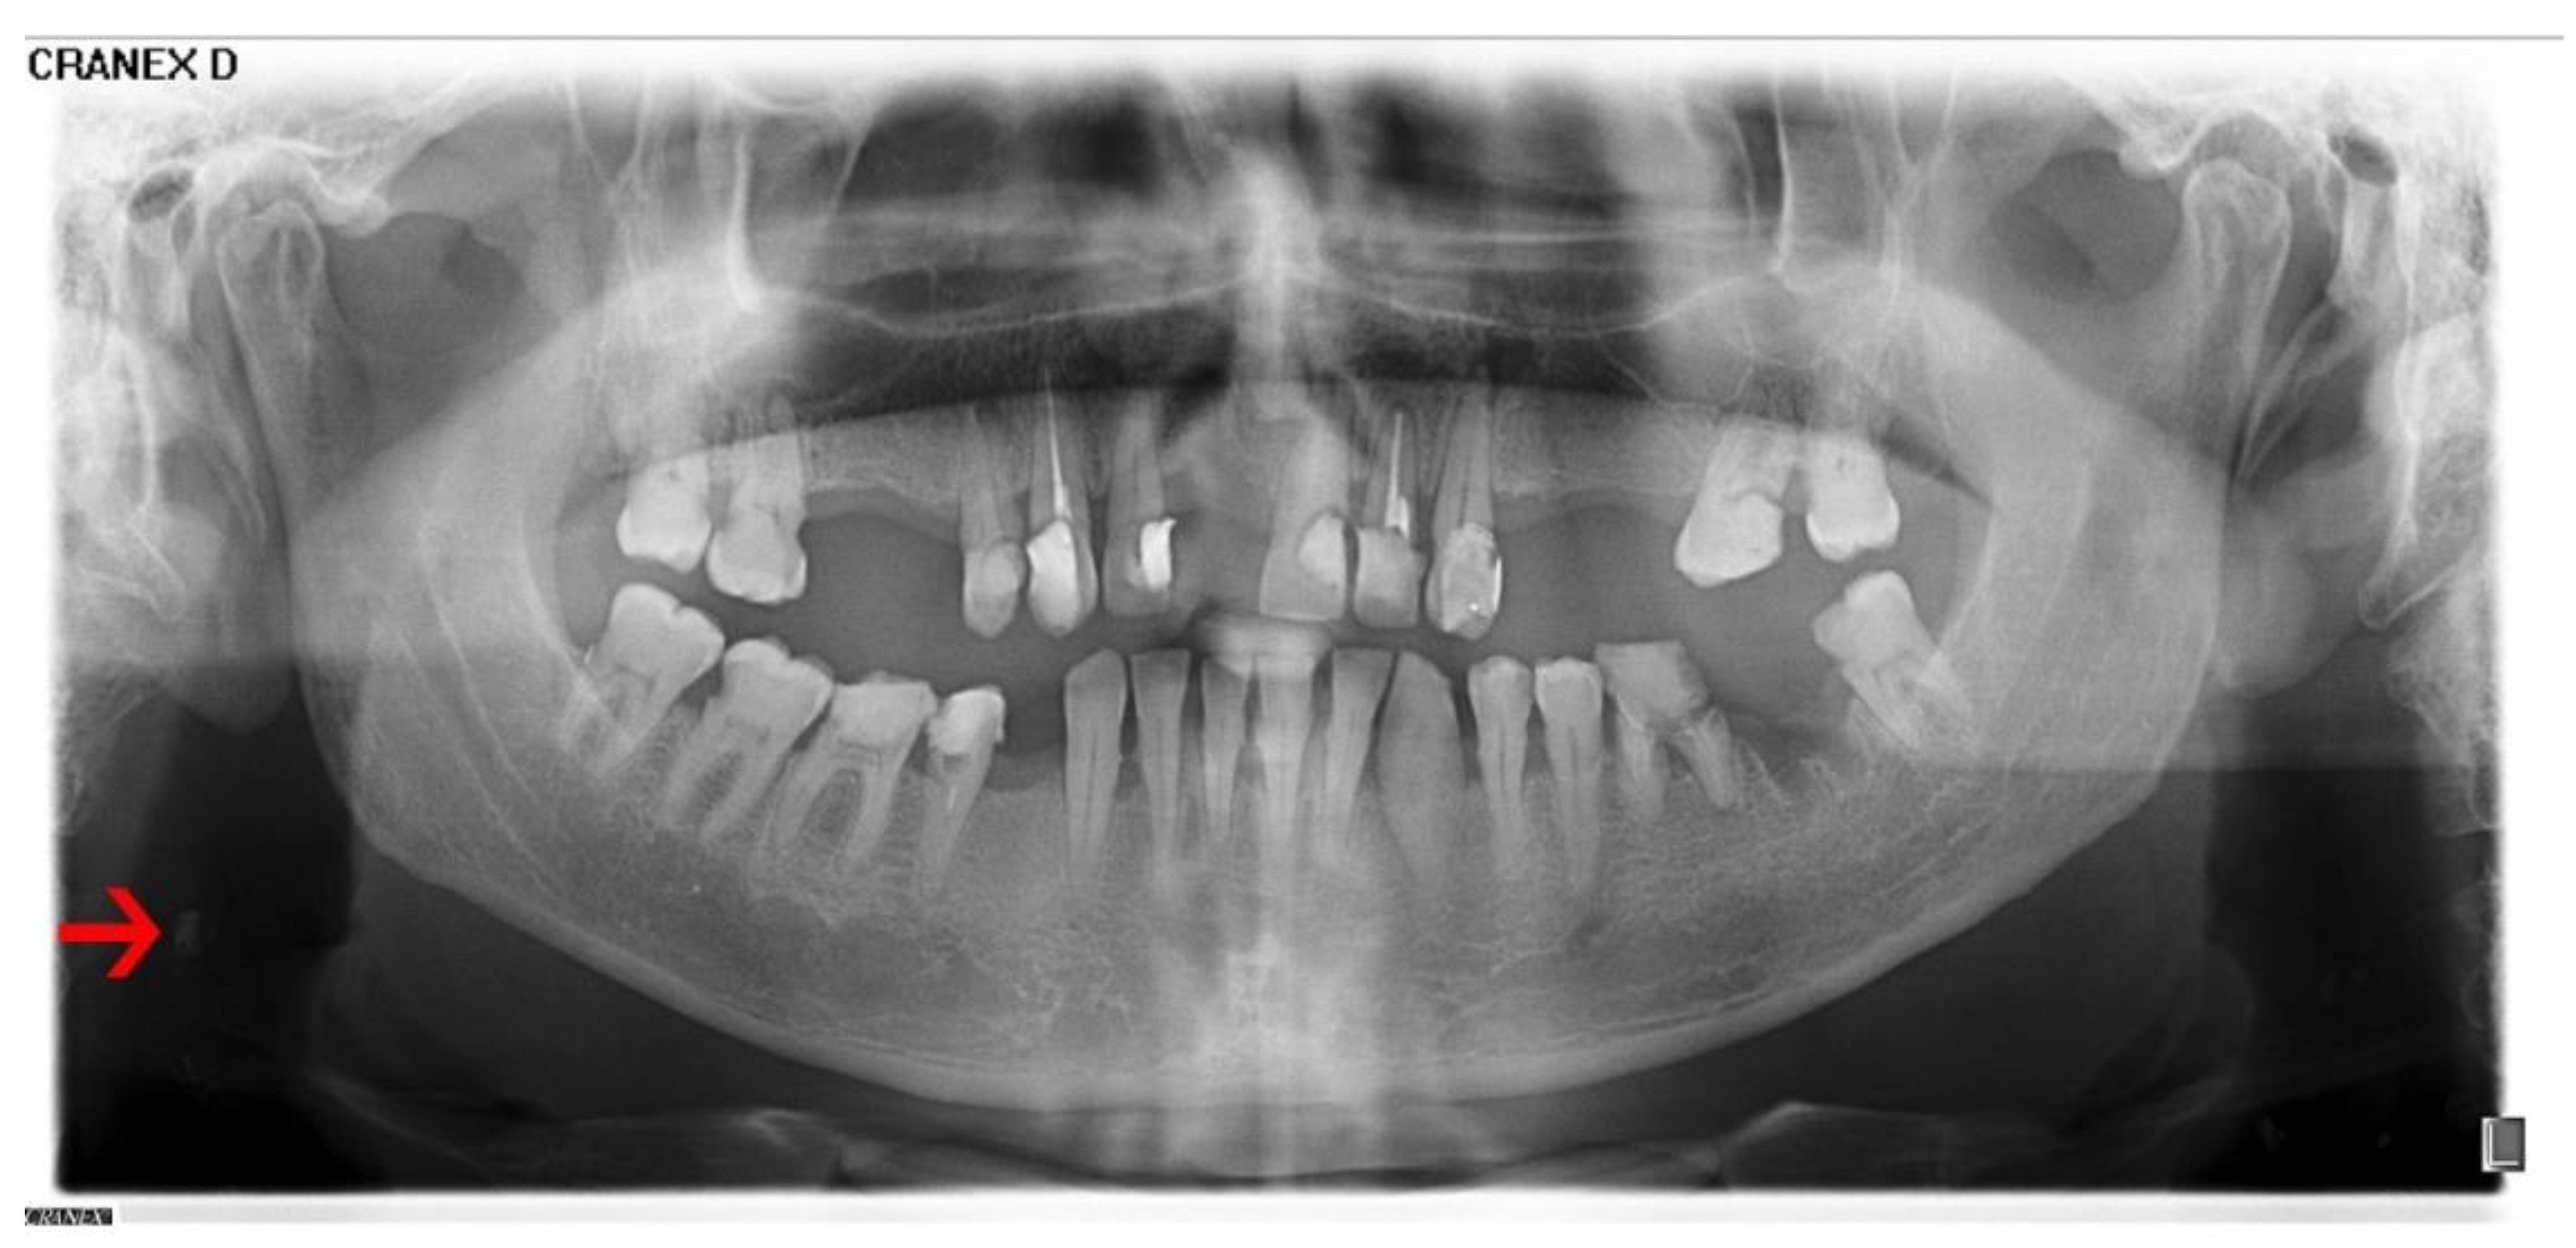

2.2. Radiograph Evaluation